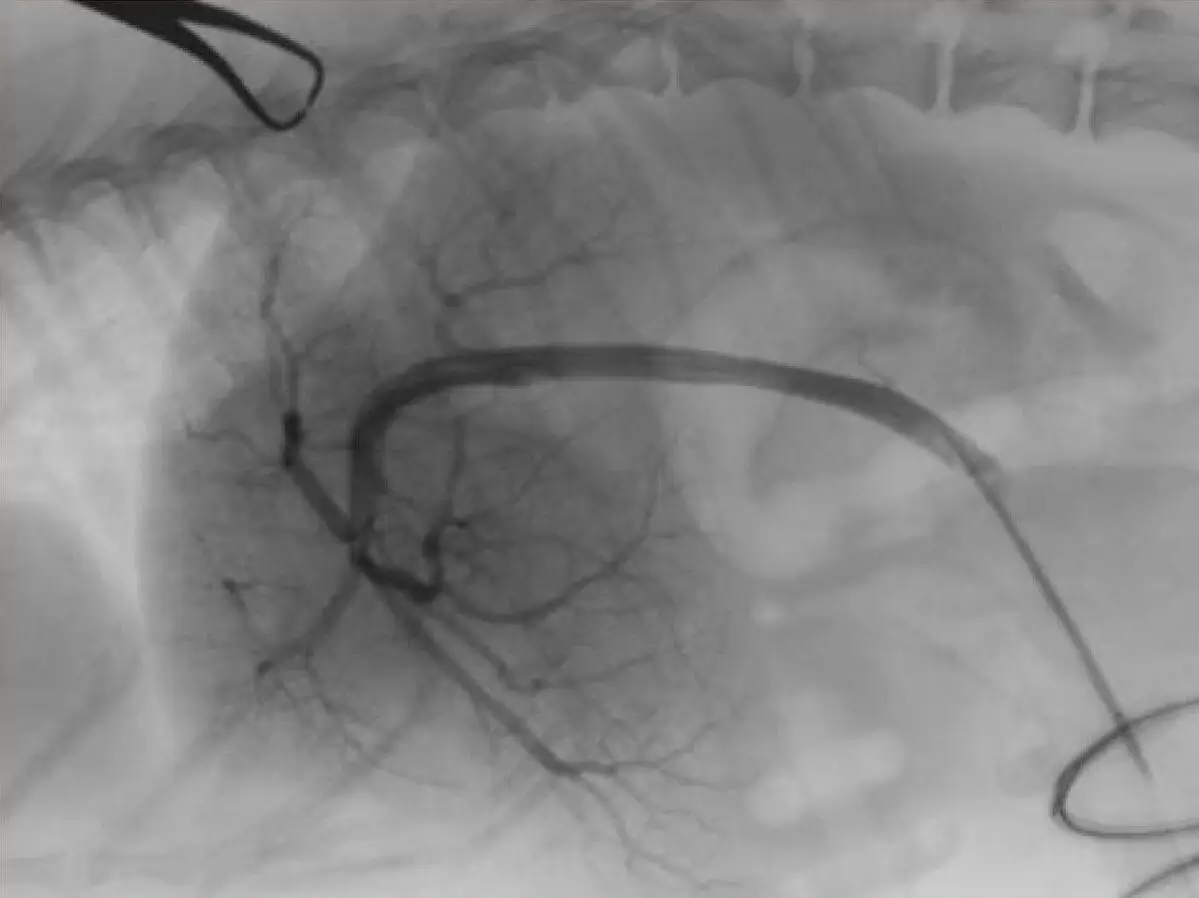

馬医療

• 馬を専門に取り扱う診療科・研究室を設置している唯一の私立大学!

• 年300例以上の馬を診る唯一の私立大学!

• 日本最大の競走馬生産地、北海道日高地方へアクセスしやすい立地で、卒業生も多数馬産地にて活躍!